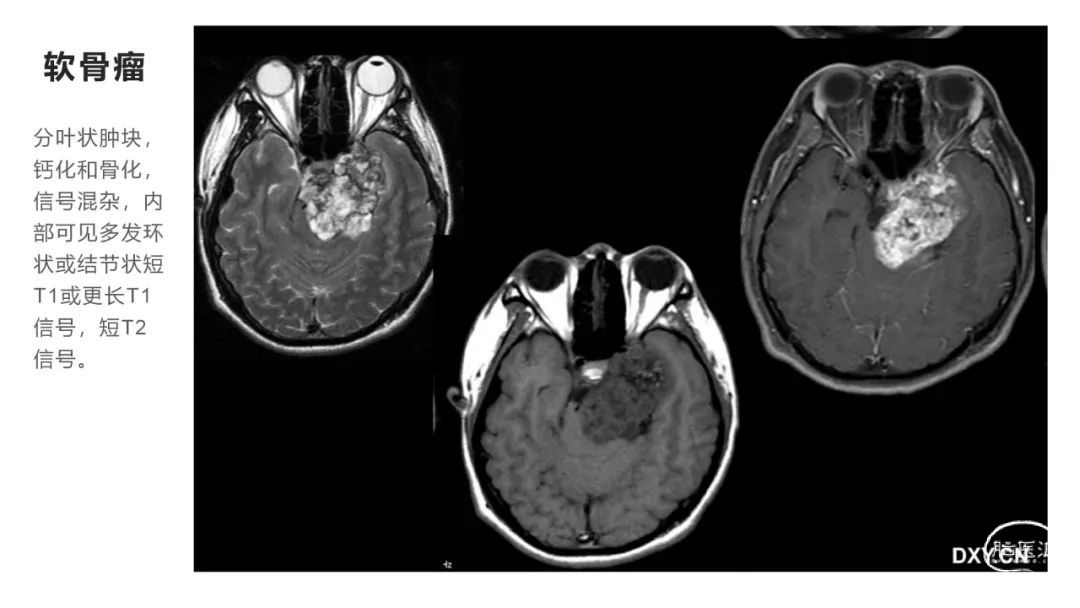

颅脑影像诊断基础知识讲座:颅骨病变